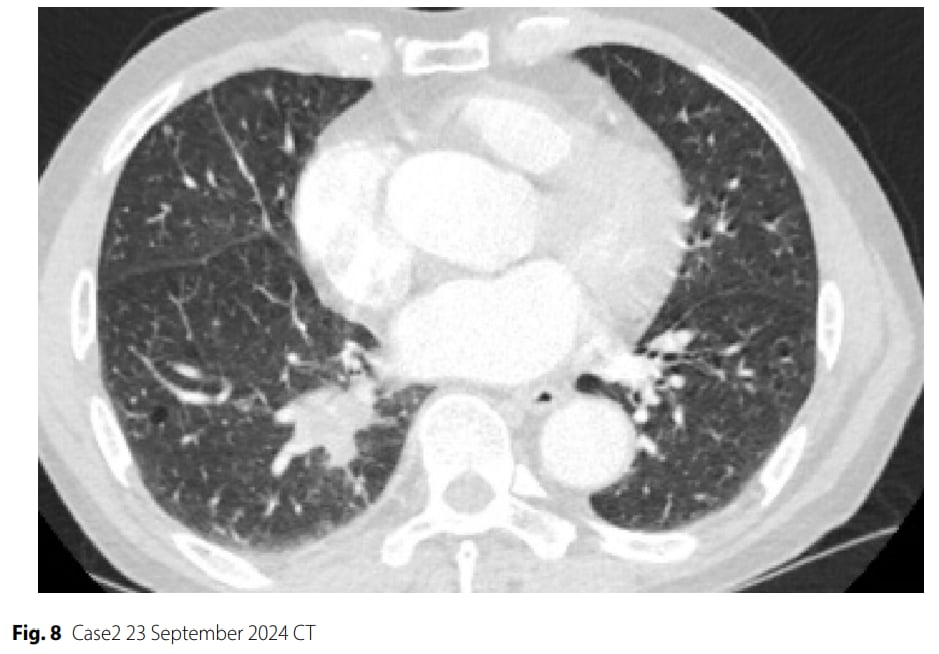

▲图8 病例2 2024年9月23日CT

治疗过程:患者接受了3个周期的“依托泊苷+卡铂+斯鲁利单抗”新辅助治疗。初期影像学显示肿瘤部分缓解(缩小68.3%),但第三个周期治疗后却出现反常进展(肿瘤增大)。影像学评估为疾病稳定(SD),具备手术切除条件。患者强烈要求手术,经多学科团队会诊,最终决定进行手术。随后患者接受了电视胸腔镜下肺叶切除术。

- 疾病进展(PD):术后病理证实仍有残留的低分化癌细胞,伴血管侵犯。

- 分子标志物恶化:术后分子检测显示,虽然MET、PTEN、MYC的变异丰度或拷贝数有所下降,但TP53基因突变丰度保持稳定。更重要的是,肿瘤突变负荷(TMB)从治疗前的23.72个突变/兆碱基不降反升至28.13个突变/兆碱基。治疗后PD-L1表达水平也升高(TPS=20%,CPS=30%)。